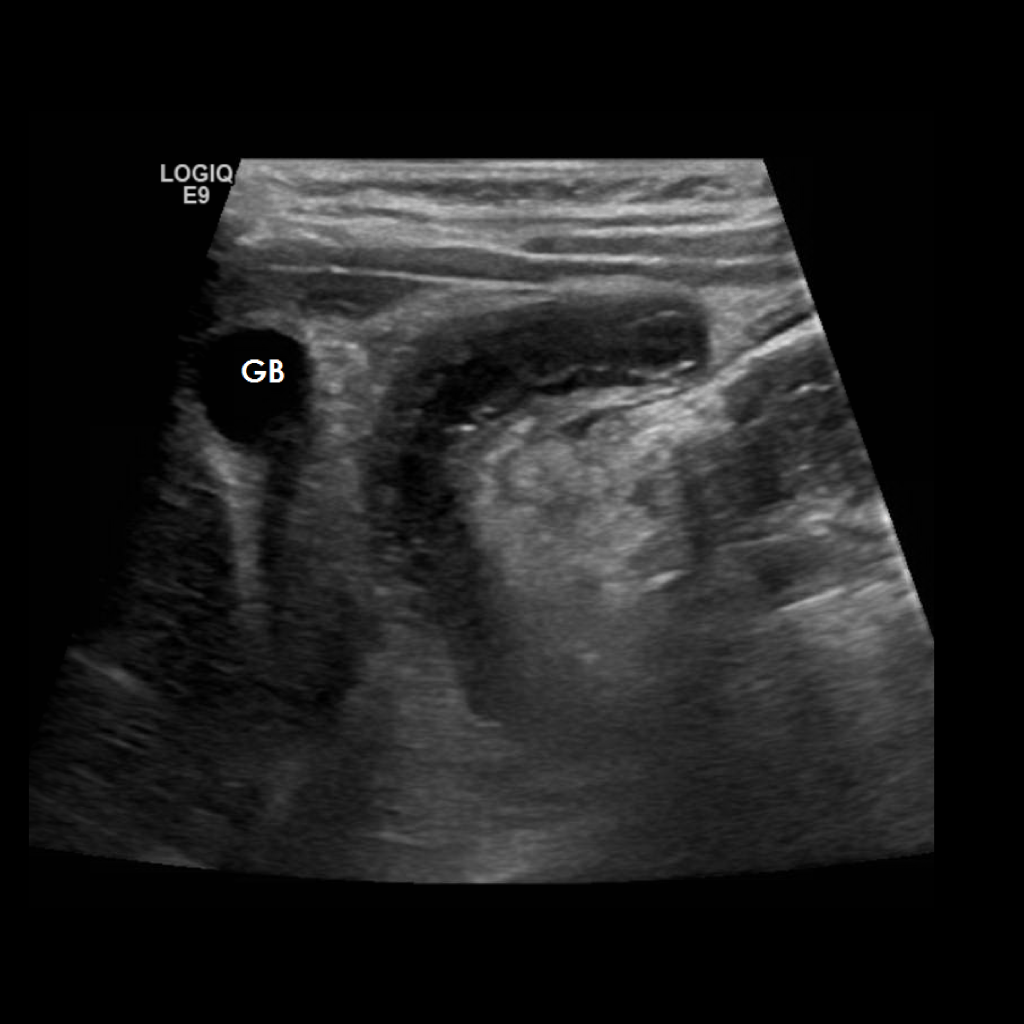

Appendicitis 10

1 cm Appendicitis located subhepatically.